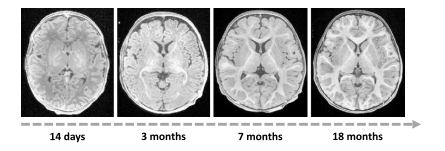

Fig. 18. Illustration of changes in both brain morphology and intensity contrastthroughout infancy

图18: 婴儿期大脑形态和强度对比度变化的图示。